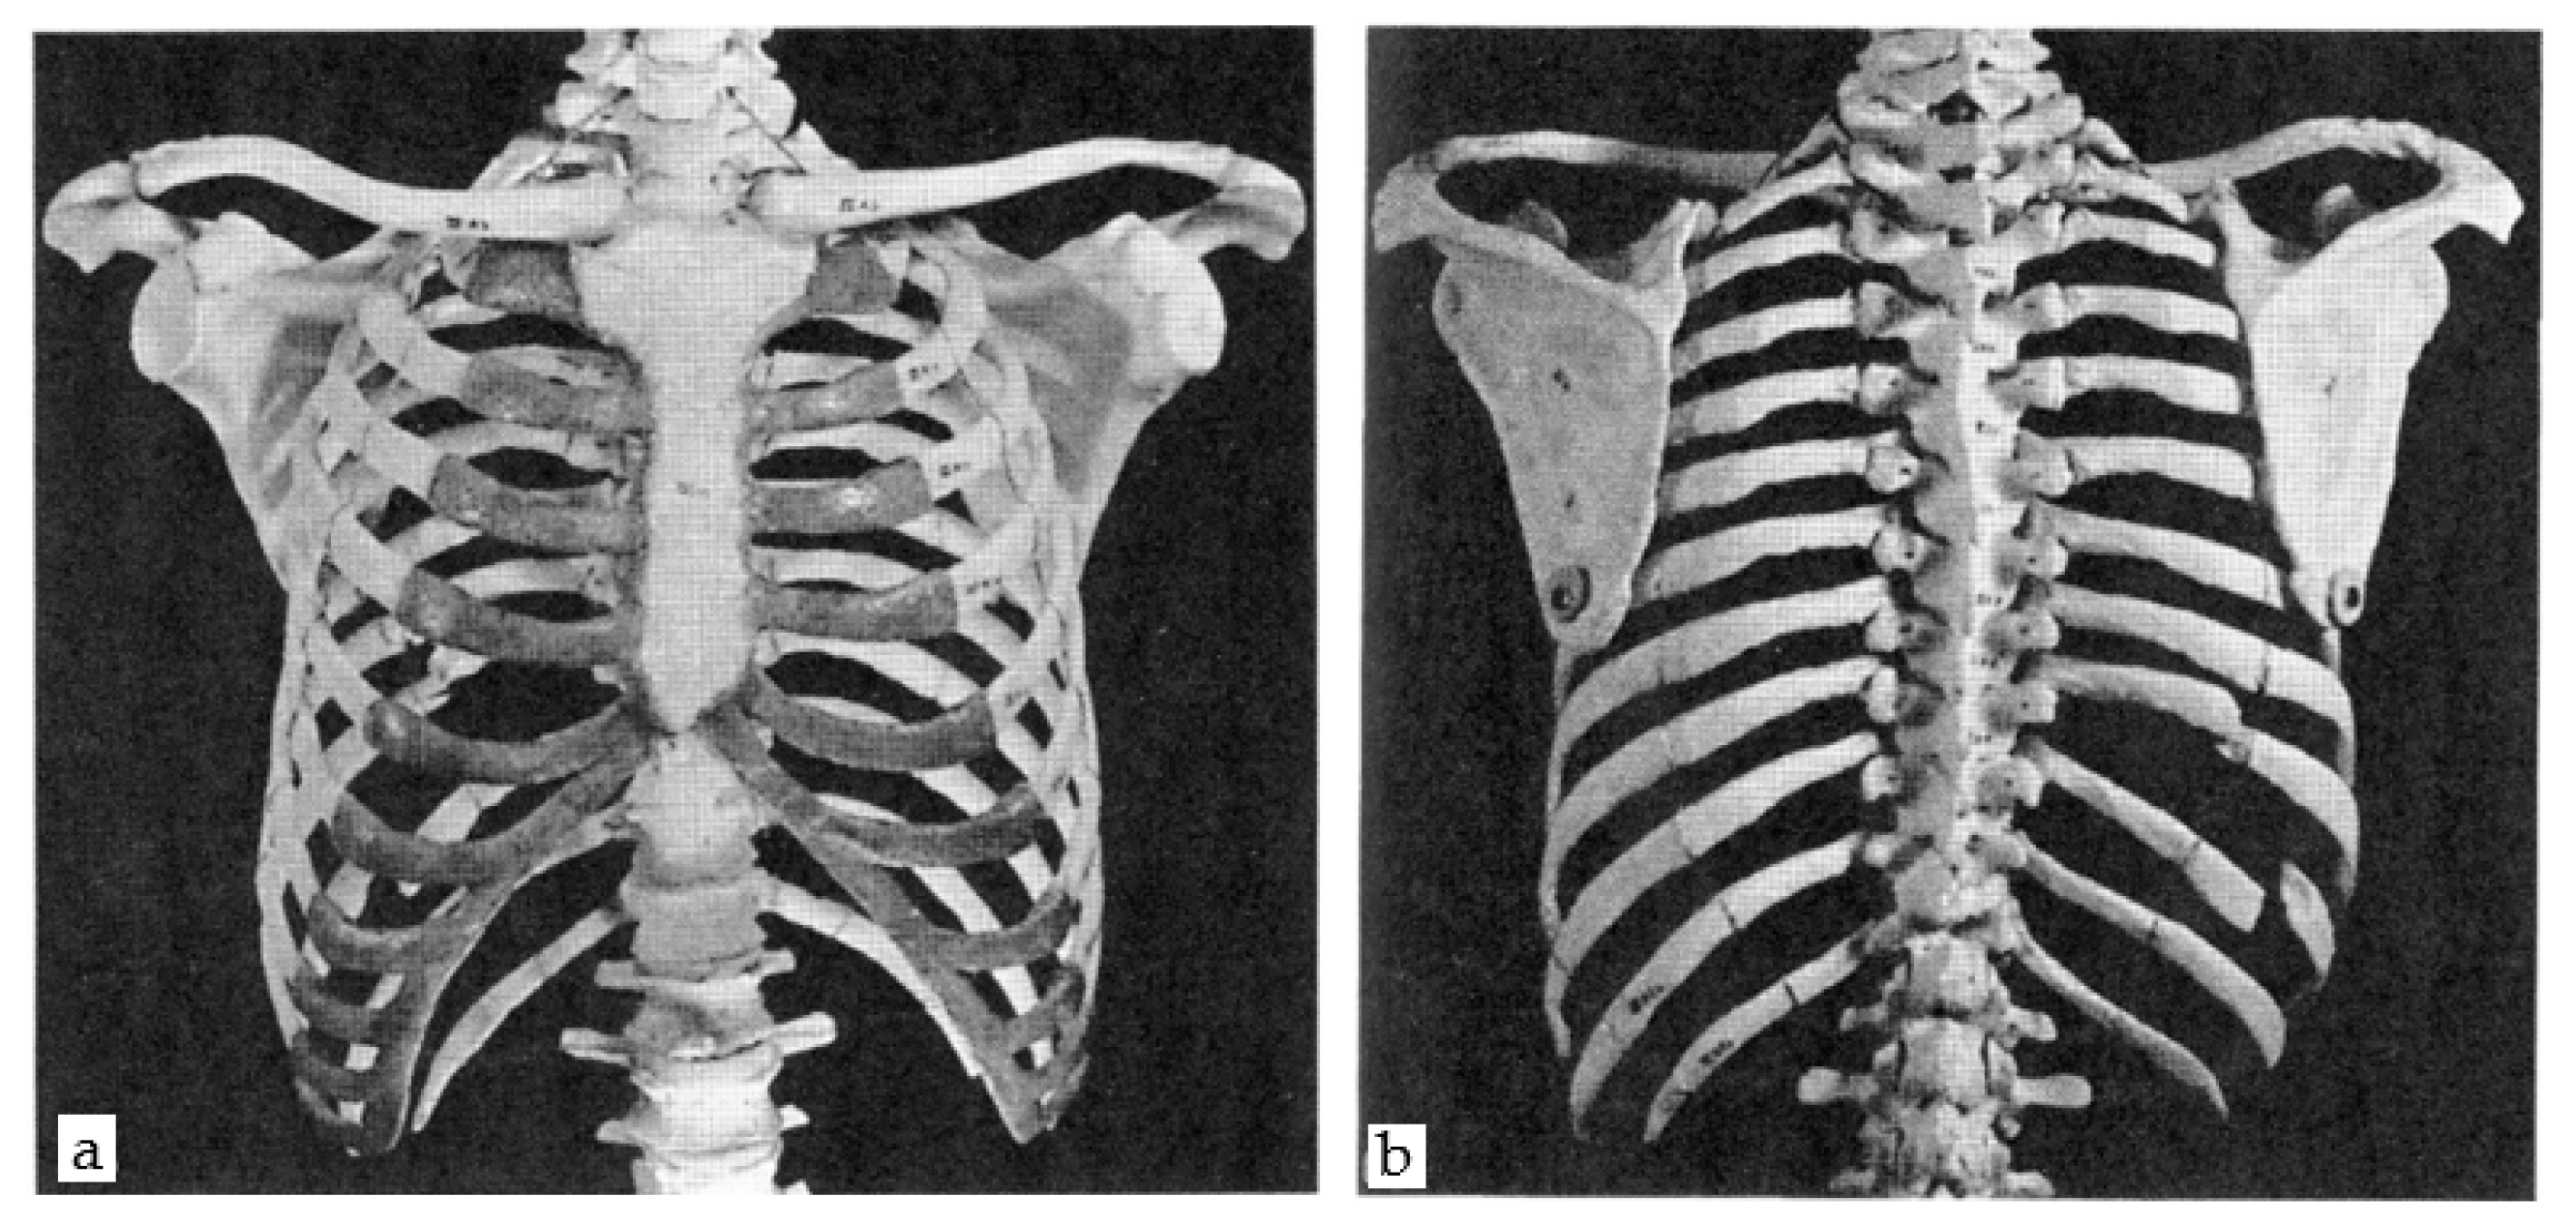

2.1.1. The Thorax

2.2.1. Generic Model–Ribs Model

2.2.2. Generic Model–Sternum Model

3.1. 3D Modelling of Thorax without Any Scoliosis-Related Deformity